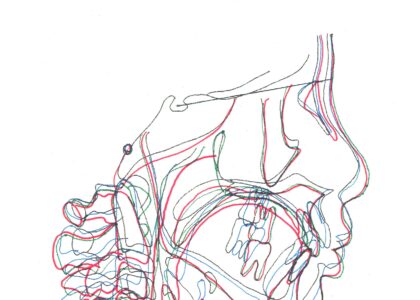

- セファロ